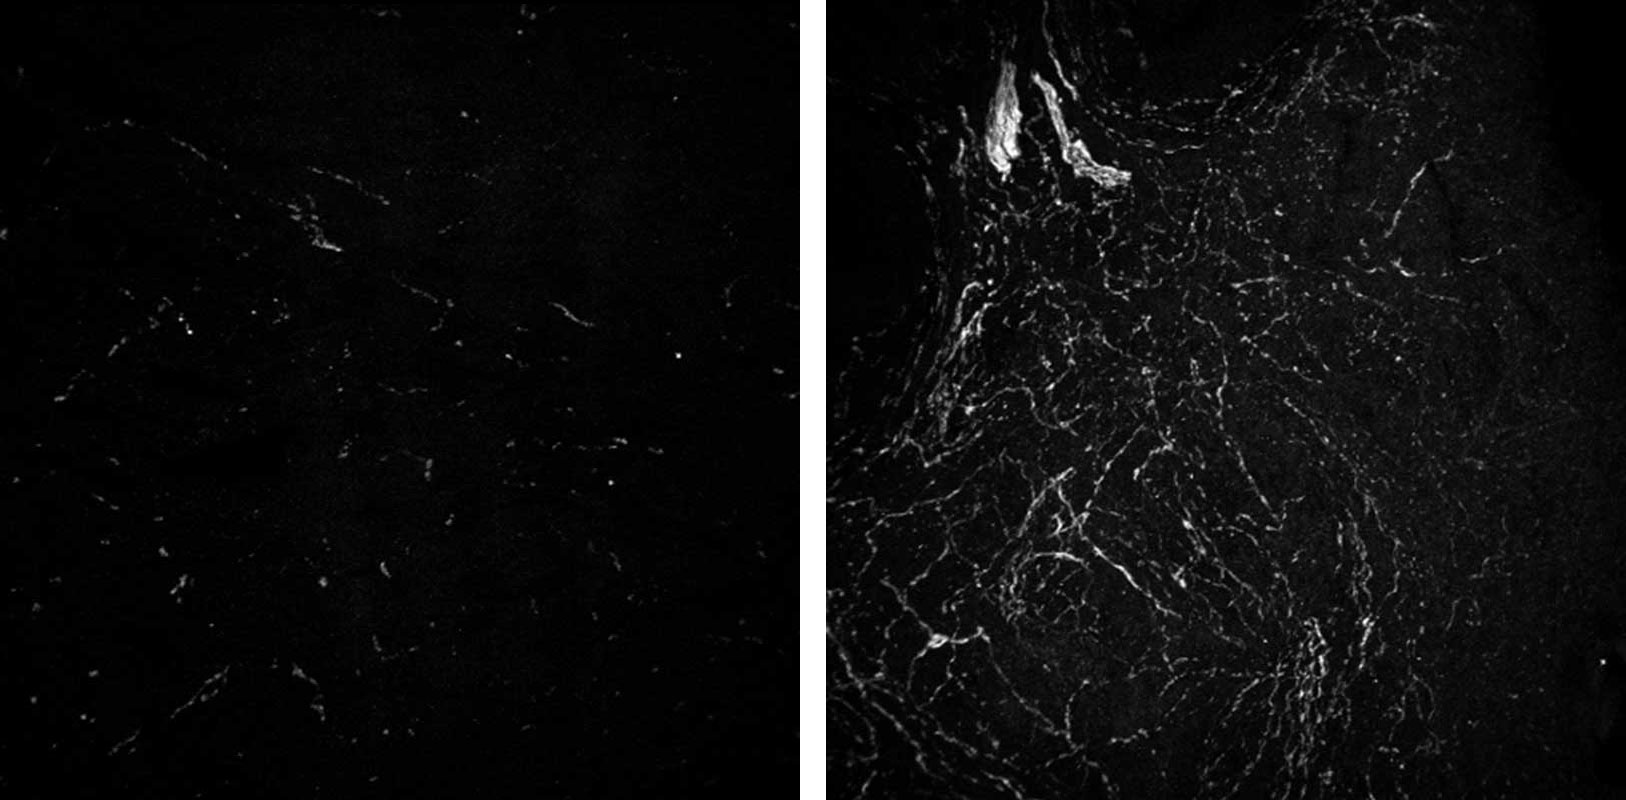

Laird and her colleagues set out to profile what normal aging looks like in the ovaries of mice and humans. First, they developed a new three-dimensional imaging technique that allowed them to visualize eggs in the ovaries without having to slice the organs into thin layers, as had been done before.

When the scientists extended their 3D imaging to human ovaries, they uncovered an unexpected finding: Eggs are not evenly scattered throughout the ovary. Instead, they cluster in “pockets” surrounded by egg-free zones. With age, the density of eggs within these pockets declines.

“This was a surprise. We assumed eggs would be distributed more evenly based on what we see in the developing ovary,” said Laird, who is a Biohub investigator and a member of the Eli and Edythe Broad Center of Regeneration Medicine at UCSF. “These pockets suggest that even within one ovary, the environment around an egg may influence how long it lasts and how well it matures.”

At the same time, the study revealed that sympathetic nerves — the same nerves involved in the “fight or flight” response — form dense networks in ovaries that become even more dense with age. When the researchers ablated these nerves in mice, the animals had more eggs in reserve but fewer that matured, suggesting the nerves help decide when eggs start growing. Together, the observations on glia and sympathetic nerves suggest a new role for the nervous system in ovarian health.